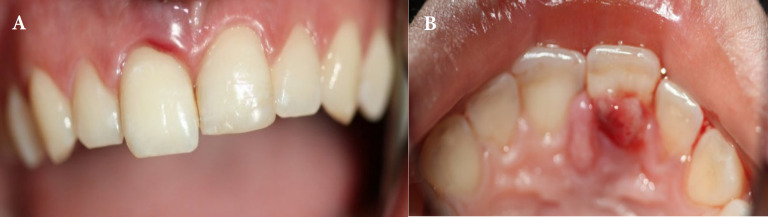

急性根尖脓肿(AAA)是一种以自发疼痛、脓形成和肿胀为特征的快速发作的炎症性疾病,通常由牙髓坏死引起。并发症可能包括全身性表现和严重的后果,如牙齿挤压。本病例报告描述了一例罕见的AAA引起上颌中切牙快速挤压的17岁女性病例。患者表现为自发的疼痛和牙齿的活动,并伴有局部肿胀。临床和影像学评估显示牙髓坏死、AAA级和根尖骨稀疏。紧急治疗开始了,包括用氢氧化钙进行管内药物治疗和暂时的牙齿夹板。随后的治疗包括用杜仲胶和密封剂进行封闭,然后进行永久性修复。5年的影像学和临床资料显示根尖周围完全愈合,牙齿活动正常,无症状复发。有效的管理,包括及时的根管治疗和夹板,导致了成功的长期结果。该病例强调了及时诊断和及时定制治疗的重要性,以管理AAA和预防严重并发症。

An acute apical abscess (AAA) is a rapid-onset inflammatory condition characterized by spontaneous pain, pus formation, and swelling, often resulting from pulp necrosis. Complications may include systemic manifestations and severe outcomes, such as tooth extrusion. This case report describes a rare instance of AAA causing rapid extrusion of a maxillary central incisor in a 17-year-old female. The patient presented with spontaneous pain and mobility of the extruded tooth, accompanied by localized swelling. Clinical and radiographic evaluations revealed pulp necrosis, an AAA, and apical bone rarefaction. Emergency treatment was initiated, including intracanal medication with calcium hydroxide and temporary splinting of the tooth. Subsequent treatment involved obturation with gutta-percha and sealer, followed by permanent restoration. Radiographic and clinical recalls up to 5 years demonstrated complete periapical healing, normal tooth mobility, and no recurrence of symptoms. Effective management, including timely root canal therapy and splinting, led to successful long-term outcomes. This case underscores the importance of prompt diagnosis and immediate, tailored treatment to manage AAA and prevent severe complications.